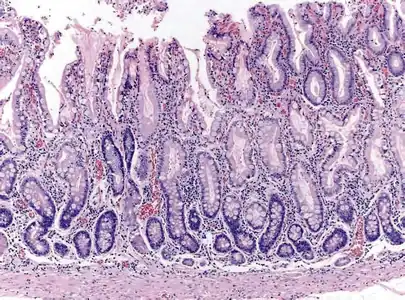

- Histopathology of fundic mucosa with atrophy. H&E 10x; square 20x. Fundic-corporal gastric mucosa with extensive loss of gastric glands, partially replaced by pseudo-pyloric metaplasia.